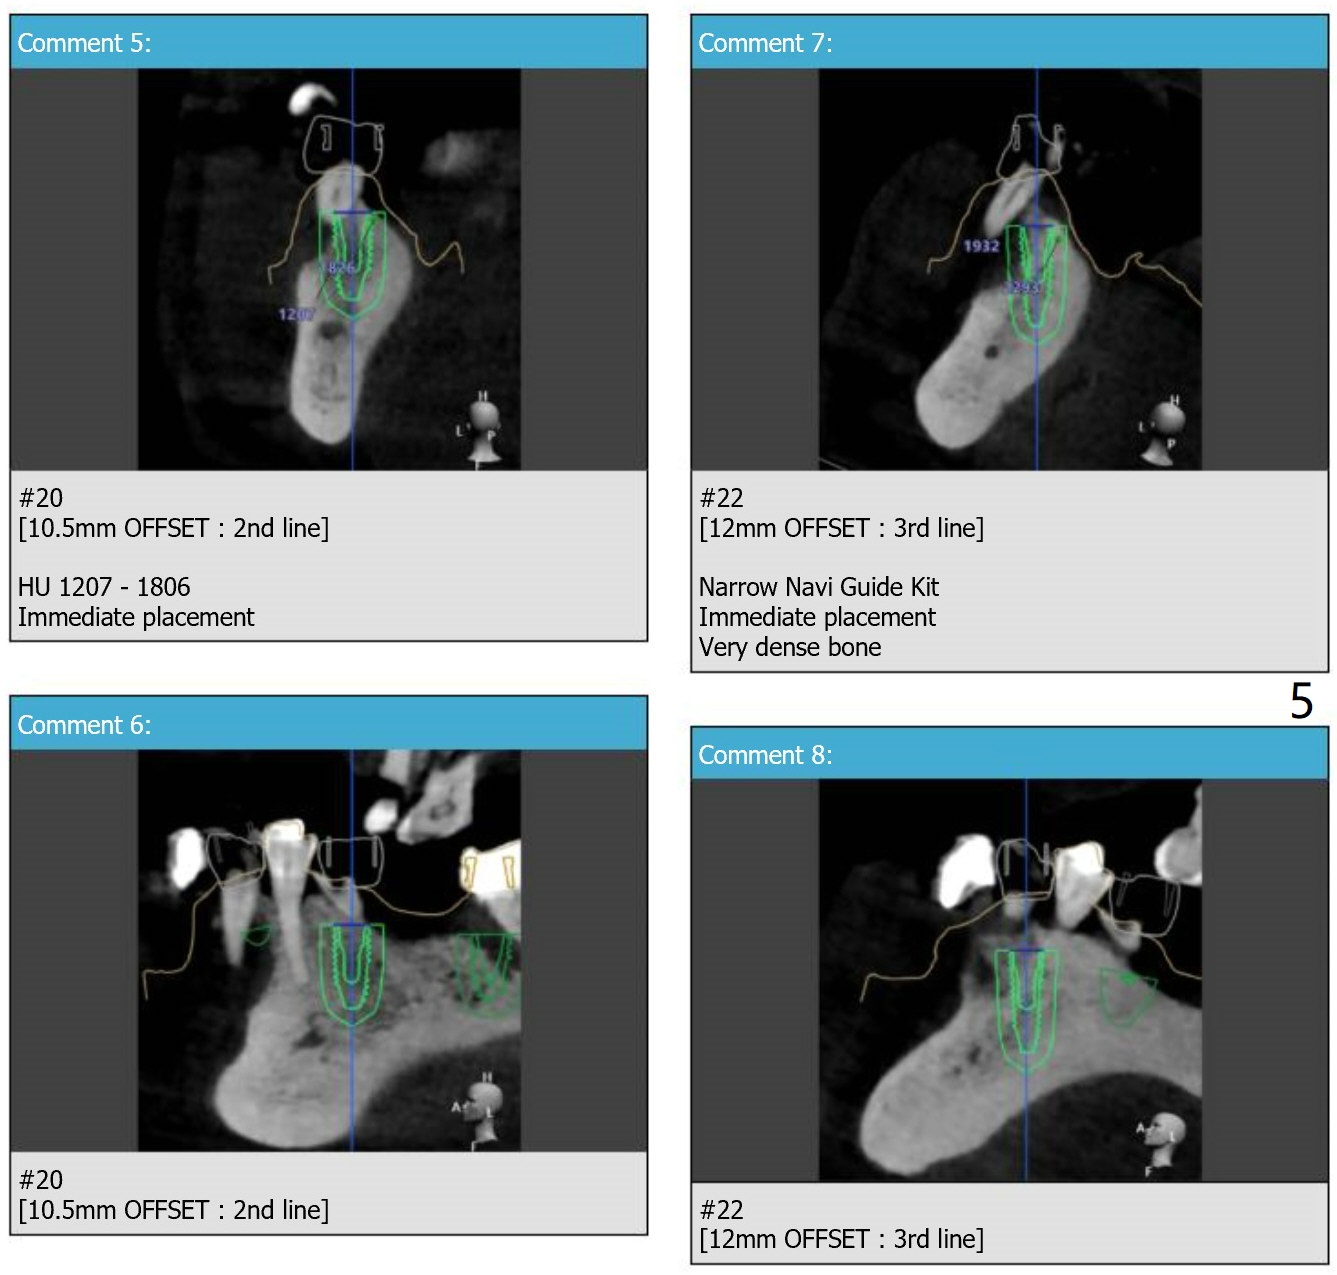

For placement of implants at #20, 22 and 27.

Immediate Implant,